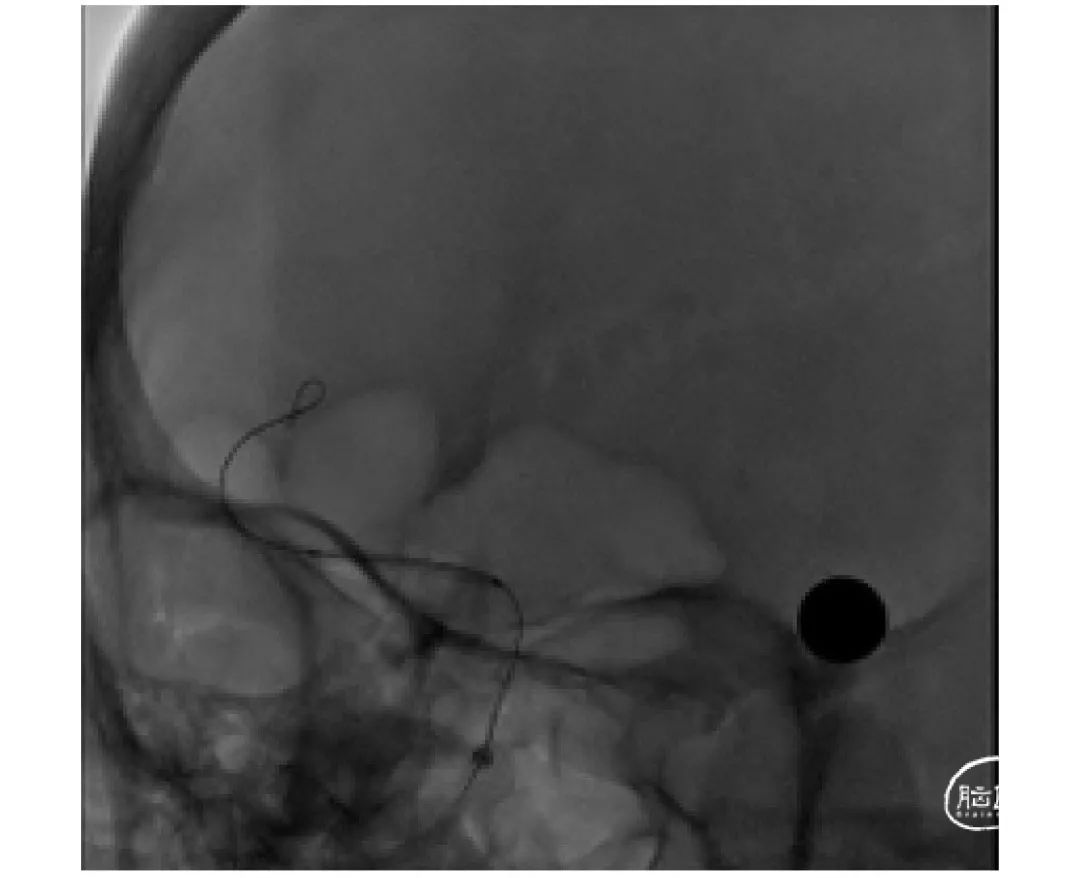

上海心玮医疗科技股份有限公司(股票代码:06609.HK)成立于 2016 年,公司致力于提高创新医疗技术的可及性,守护生命健康。六年时间,心玮医疗在神经介入领域开拓性地打造了国内首个卒中治疗及预防一站式解决方案,拥有从急性缺血性卒中和神经血管狭窄治疗、缺血性卒中预防、出血性卒中治疗到介入通路器械的全产品管线,申请专利超过 100 项,产品年产能超过 15 万件,销售渠道覆盖国内超过 30 个省(含直辖市和自治区)的 1400 多家医院。